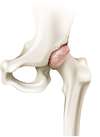

L’articulation de la hanche appelée aussi articulation coxo-fémorale met en relation la cavité articulaire du bassin (Cotyle) et la tête fémorale. Ces deux structures sont fermement emboîtées et sont entourées d’une capsule articulaire, de puissants ligaments et d’une chape musculaire. La mobilité de la tête fémorale dans le cotyle est facilité par le cartilage qui recouvre les deux surfaces osseuses et par le liquide articulaire ou synovial qui améliore le mouvement et nourrit le cartilage.

L’arthrose désigne un processus d’usure du cartilage liée au vieillissement. Ce n’est pas une fatalité liée à l’âge. Elle cause des dommages irréversible du cartilage qui perd au fur et à mesure son rôle de surface de glissement et d’amortisseur. La pression sur l’os s’accroît à mesure que l’épaisseur cartilagineuse diminue. Des excroissances osseuses, appelées ostéophytes, des kystes osseux et des ulcérations cartilagineuses se forment progressivement.

En réponse, la membrane synoviale devient inflammatoire et produit un liquide synovial. L’excès de pression articulaire et l’inflammation sont les causent des douleurs de hanche. La perte de congruence de l’articulation entraîne quant à elle, une diminution de la mobilité articulaire.